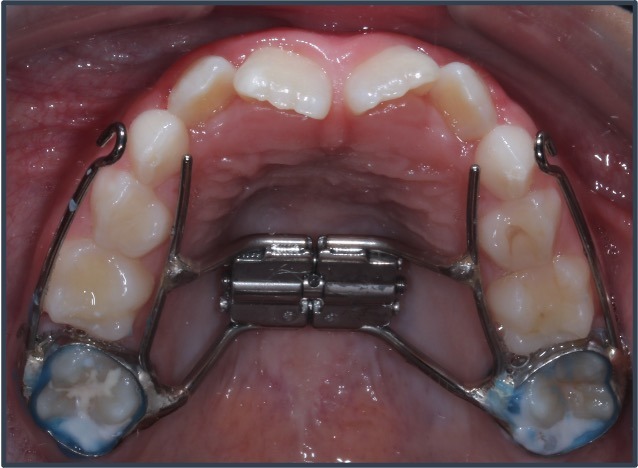

If your child has a narrow palate or crowded teeth, a device called a palatal expander can gently widen their upper jaw. It creates more room for teeth to grow in straight (yay!!). But (bonus!) it also expands the nasal airway above, which helps kids breathe better through their nose.

Parents often report their child sleeps more quietly and wakes up more rested after expansion. It’s a small step that can make a big difference in behavior, focus, general health, and development for all our El Paso kids.